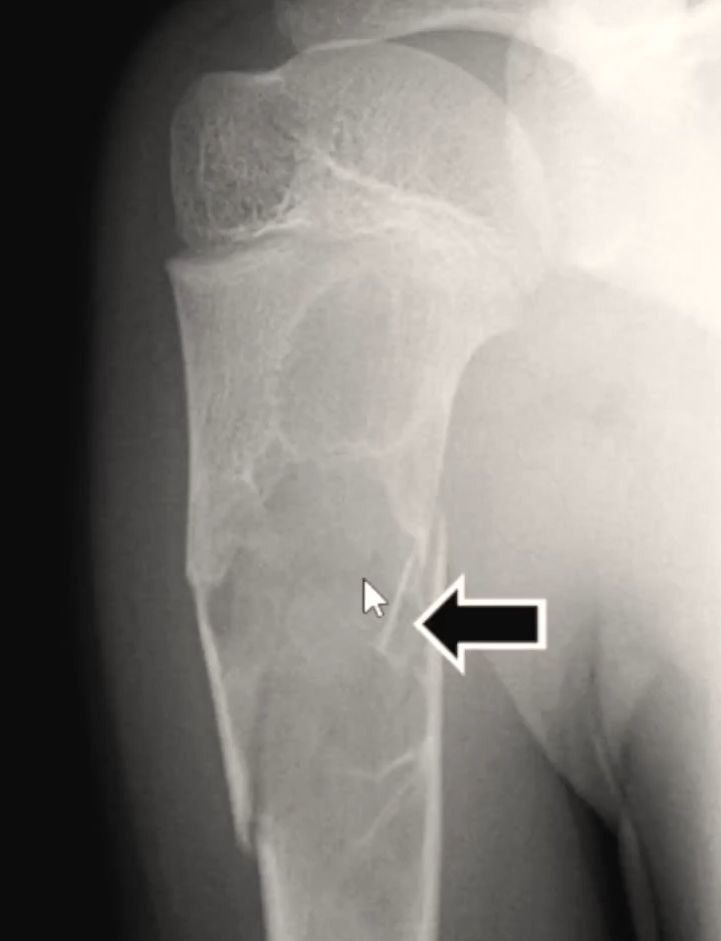

Как выглядят остеофиты и экзостозы?

В классической парадигме остеофиты и экзостозы рассматриваются как патологический процесс, что-то пошло не так, и сформировался нарост.

На картинках мы видим, что как будто выросла новая кость, маленькая косточка отпачковывается от большой.

Можно предположить, что это некая неоплазия, новое образование, иначе говоря. То есть клетки вдруг решили избыточно поделиться. И так как это кальцифицированное образование, то мы могли бы предположить, что это избыток кальция, как это сейчас рассматривает традиционная парадигма. Но она не объясняет, почему экзостоз вырос именно в этом месте и почему именно сейчас? Что вообще там происходило? Это объясняет только моя любимая парадигма ГНМ. Германская новая медицина мне позволила абсолютно полностью понять природу остеофитов и экзостозов и разобраться, что вообще с этим всем делать и делать ли.

И когда у нас формируется каллус, даже если это была трубчатая кость, длинная кость, плоская кость, сначала на месте каллуса формируется хрящевое образование. Потом этот хрящ превращается в губчатую костную структуру. То есть это косточка с множеством трабекул, трубочек, иначе говоря. И в процессе удаляются фрагменты гематомы. И вот то, что получилось, называется костная мозоль. происходит кальцификация каллуса, и формируется костная мозоль.